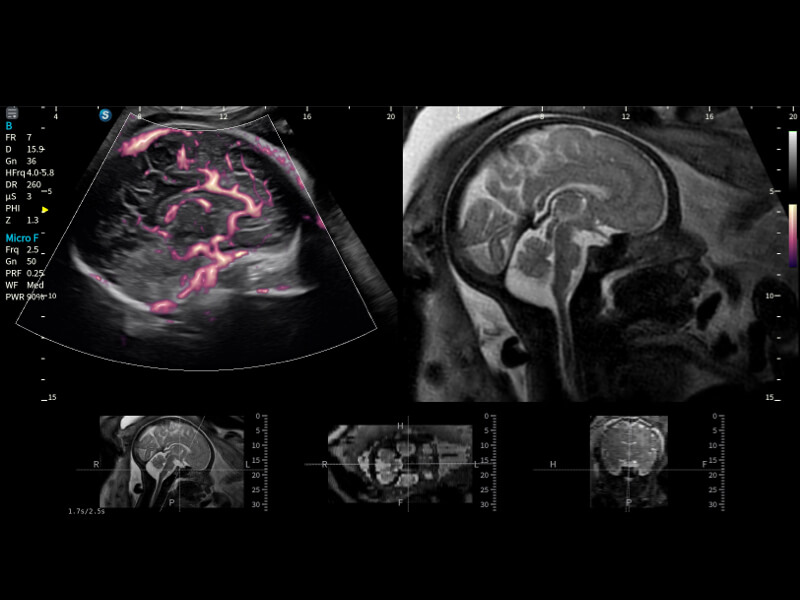

豐富的血流動(dòng)力學(xué)檢測(cè)技術(shù),可在不同醫(yī)療場(chǎng)景中高效捕捉血流信號(hào),助力臨床診療。

在傳統(tǒng)血流的基礎(chǔ)上優(yōu)化掃查和算法策略,能夠更好的抑制組織信息,提煉紅細(xì)胞運(yùn)動(dòng)信息,得到更高幀頻,高靈敏度和分辨率的血流信號(hào),還原更真實(shí)的血流動(dòng)力學(xué)。

通過(guò)光照模型,使二維血流顯示出立體的效果,增加血流的敏感性、成束性,減少外溢??梢院推渌煌难骷夹g(shù)聯(lián)合使用,融合不同技術(shù)的優(yōu)勢(shì)。輕松應(yīng)對(duì)微小血管,增強(qiáng)血流的立體效果,提升視覺(jué)敏感性。

通過(guò)創(chuàng)新的Matrix E自適應(yīng)濾波算法,能有效濾除軟組織和噪聲信號(hào),最大限度保留超低速微細(xì)血流的信號(hào);結(jié)合超長(zhǎng)時(shí)間域算法,極大提升細(xì)微血流的敏感性和空間分辨率,更真實(shí)的反應(yīng)組織、包塊的血流灌注情況。